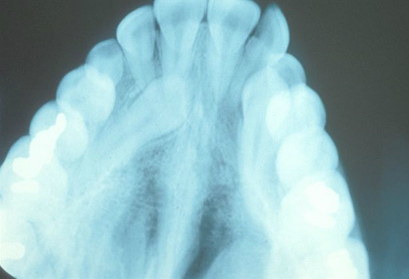

Any tooth which either only partially erupts or does not erupt on time is said to be impacted. This is usually due to a lack if space but can also be from non-resorbing baby teeth, trauma, or fusion to the surrounding bone. Though the most common example of impacted teeth are the wisdom teeth (3rd molars), any tooth is susceptible to impaction. Once identified, It is important that the condition be corrected as early as possible in order to prevent a deeper impaction, damage to adjacent roots, or development of a more severe malocclusion.

Usually the impacted tooth is exposed over the course of a few months and brought into the correct position of the mouth. Correction of impacted teeth may involve a minor surgical procedure performed by an oral surgeon working closely with our practice. This will allow us to then guide eruption of the impacted tooth into proper position.